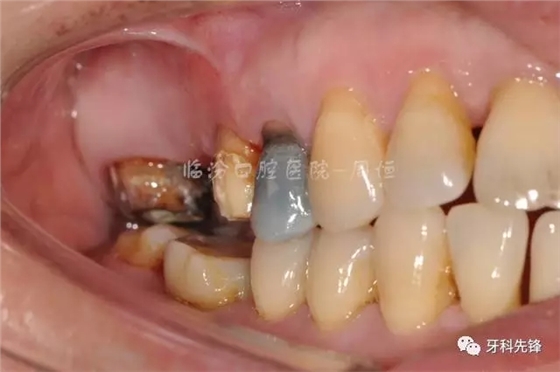

圖2 術(shù)前側(cè)位咬頜照

640.webp (3).jpg